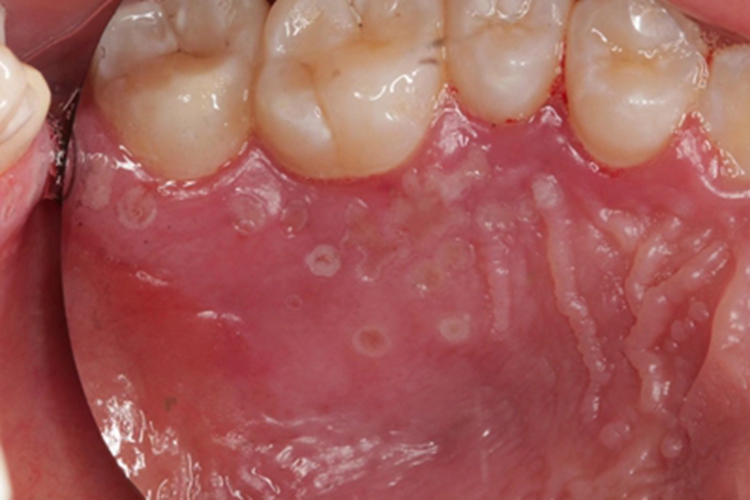

原发性口腔单纯性疱疹发病前常出现发热、头痛等不适,可见口腔黏膜任何部位皆会发生成簇水疱,发生在牙龈下时,似针头大小,水疱疱壁薄、透明,不久溃破,形成浅表溃疡。